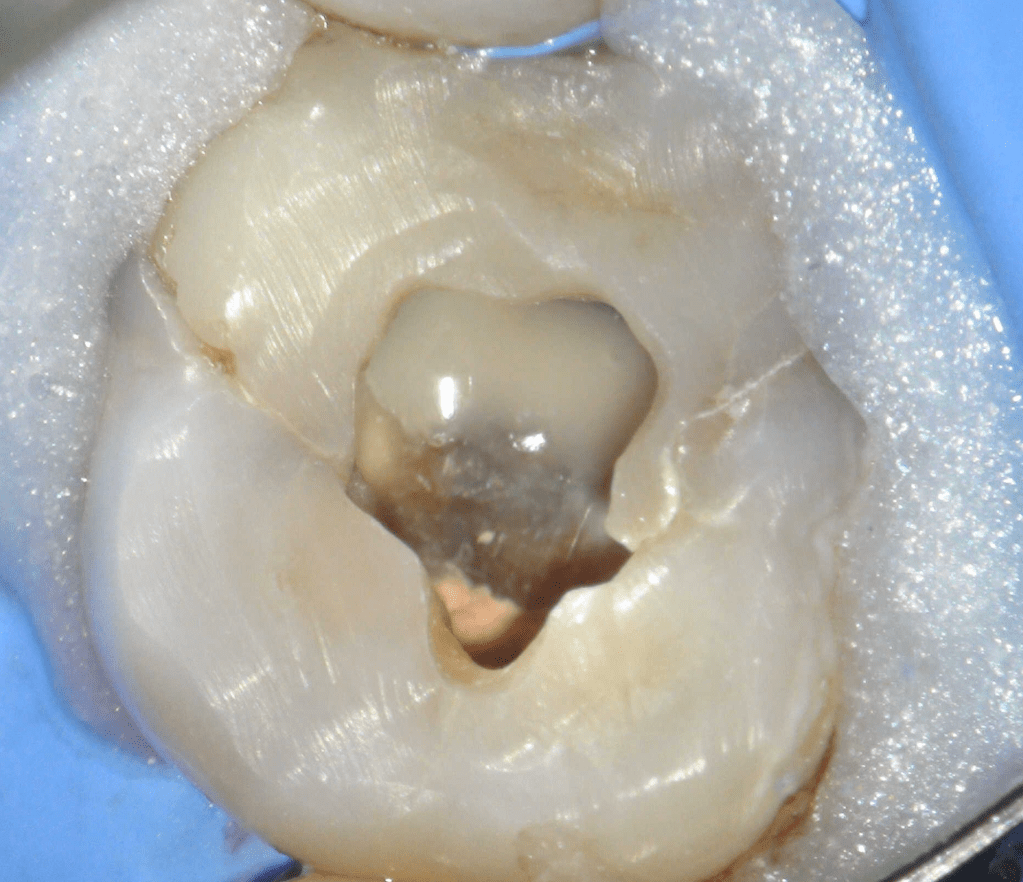

Reco preendo + 4 conductos molar superior